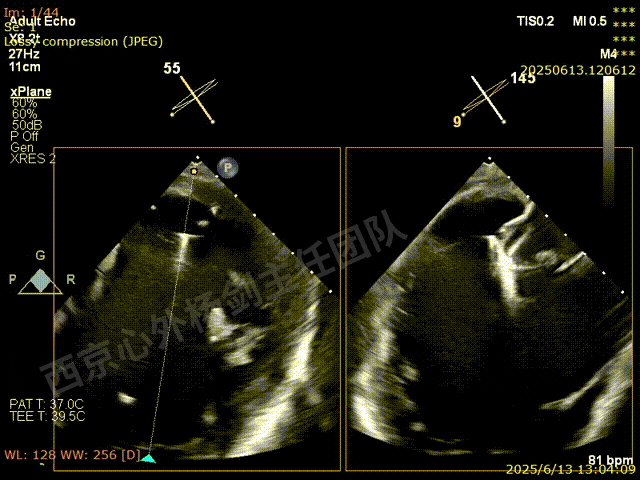

术前超声检查

图片

TAVR术后,全心增大,二尖瓣反流重度,三尖瓣反流重度。中量心包积液。左室严重增大,标准图像调整困难。主动脉瓣位带支架人工瓣膜瓣叶启闭正常,主动脉瓣位人工瓣上血流速度Vmax 148cm/s,PGmax 9mmHg,Vmean 86cm/s,PGmean 2mmHg, VTI 34.7cm,瓣周反流(轻)。估测肺动脉收缩压约49mmHg;左室收缩功能明显减低。LVEF:23%,EDV:364ml,ESV:221ml。

彩色血流示:二尖瓣反流缩流颈彩宽6.6mm,面积17cm²,容积30ml;二尖瓣瓣口面积6.6cm²,瓣环内径:左右径34mm,前后径34mm。2区瓣叶长度:前叶36mm,后叶20mm,叶环比1.6. 三尖反流面积17.2cm²,容积33ml,Vmax 291cm/s,PGmax 34mmHg。